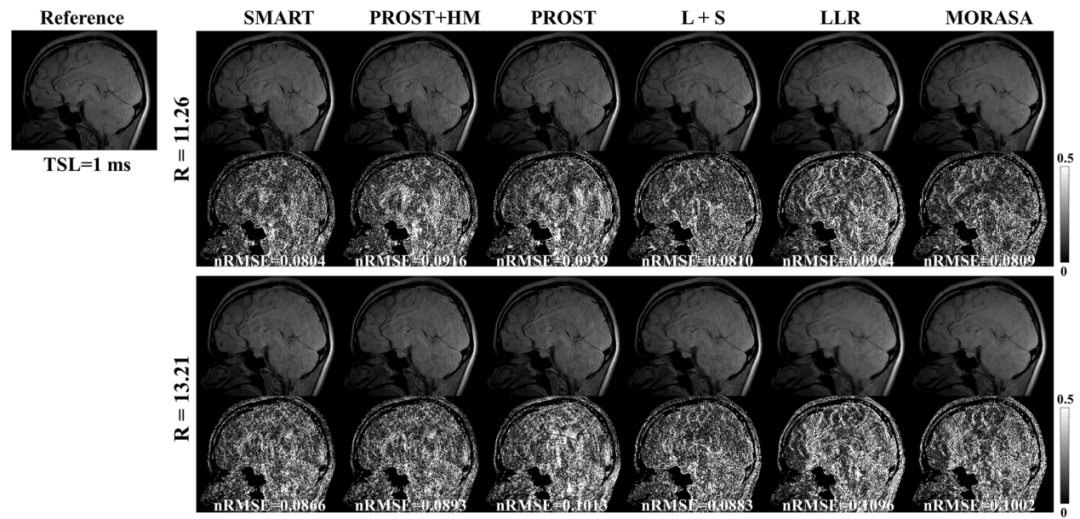

此外,磁共振驰豫值是其重要的物理参数,可以表征组织的一些生理信息,团队基于该物理弛豫先验和图像的结构相似性,提出了基于低秩张量的快速磁共振T1ρ驰豫定量方法(SMART),将扫描时间由全采样数据所需的49.9分钟缩短至3.8分钟,且在高达13.2倍加速倍数下仍能取得与全采样数据相当的图像,且重建误差小于现在主流的重建方法(图3)。相关研究工作发表在医学成像领域著名期刊IEEE Transactions on Medical Imaging。

图3.不同加速倍数下(R=11.26, 13.21)所提的SMART方法与其他主流方法的重建结果对比。